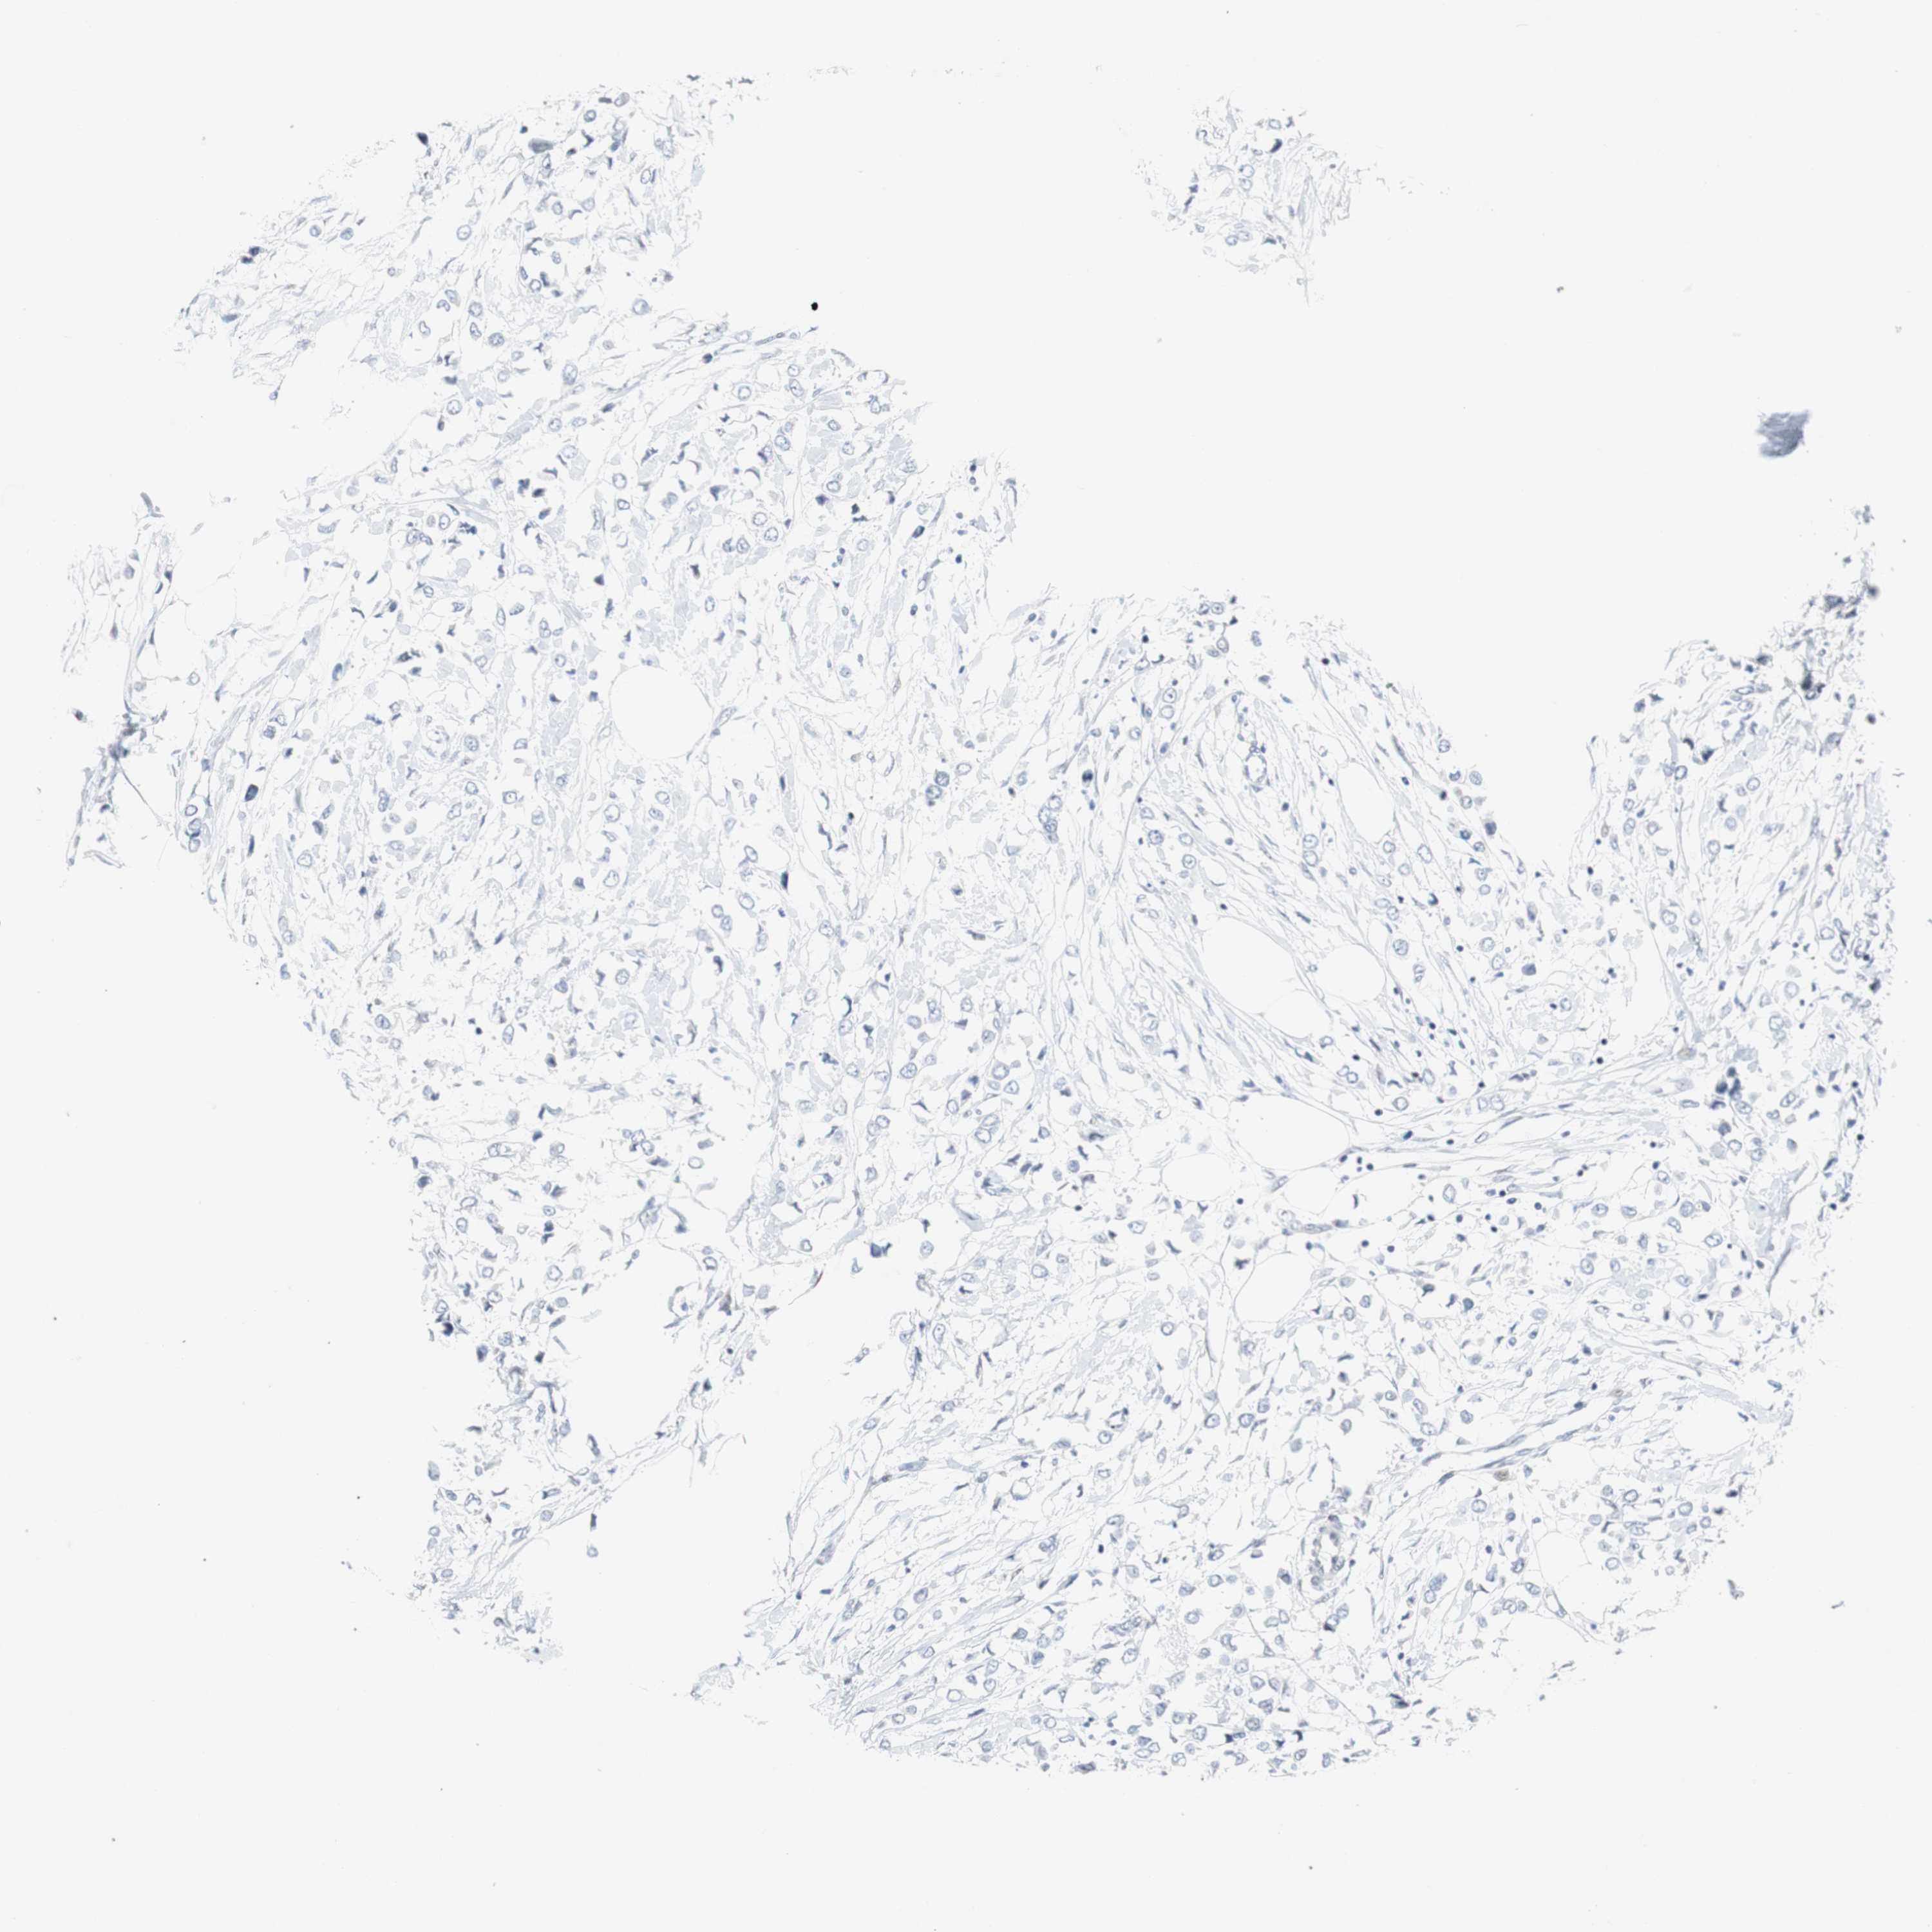

BRCA TCGA BRCA VALIDATION PROTEIN EXPRESSION

ANTIBODIES

AND

VALIDATION